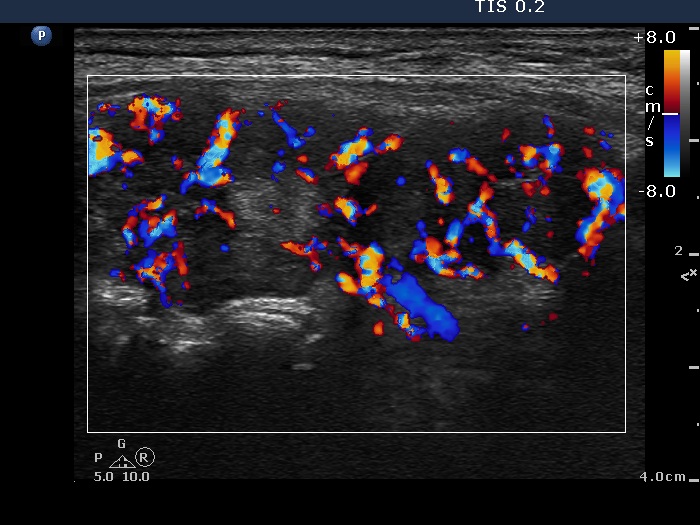

Consecutively operated patients with autoimmune thyroid disease - case 31 (17) (ultrasonographic picture 9)

Left lobe, longitudinal scan, color Doppler mode. The vascularization is significantly increased.